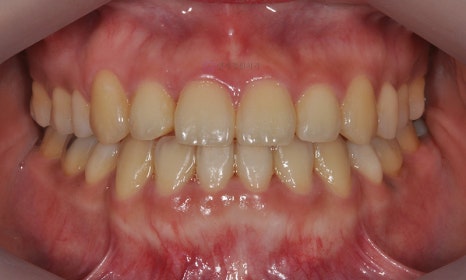

2019.5

약 17개월 동안의 교정 치료 마무리 후 사진으로, 치아 배열과 교합은 양호하게 개선되었으며, 정면 사진에서 부각되어 보이던 아래 입술 돌출도 개선되어 어려보이는 인상을 가지게 되었습니다.